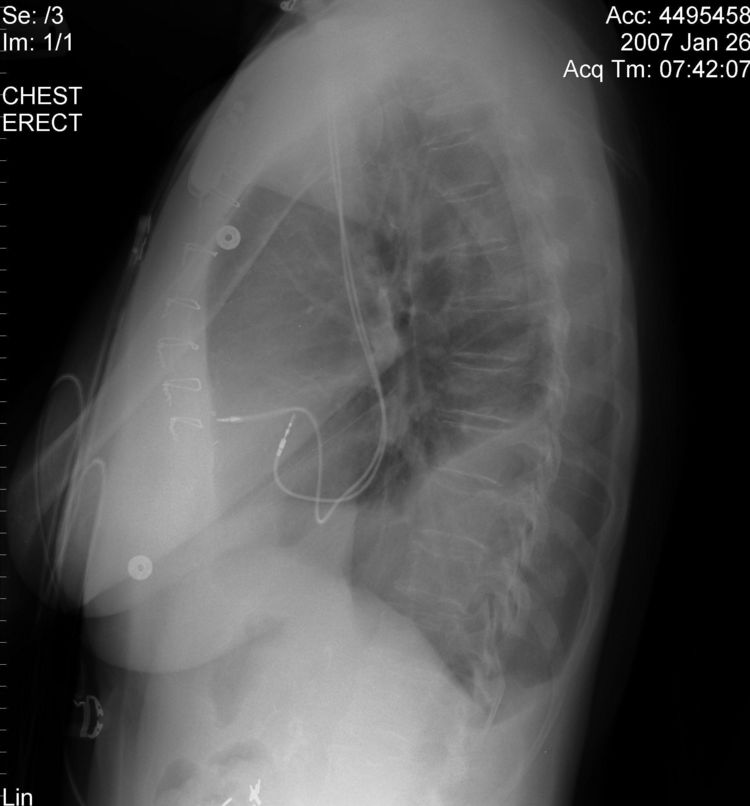

The above CXR show the atrial and ventricular pacemaker lead passing through a persistent left sided SVC.